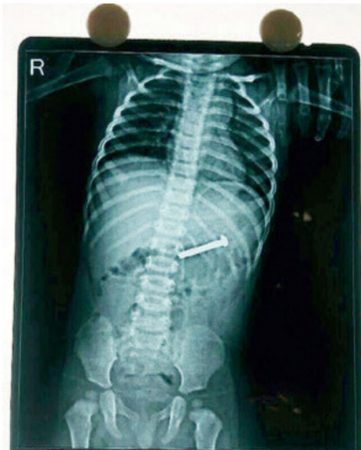

ಮಗುವು ತೊಟ್ಟಿಲಿನಿಂದ ಬಿದ್ದಿದ್ದ ಒಂದೂವರೆ ಇಂಚಿನ ಸ್ಕ್ರ್ಯೂ ನುಂಗಿತ್ತು. ನುಂಗಿದ ಬಳಿಕ ಮಗು ನೋವಿನಿಂದ ಅಳಲಾರಂಭಿಸಿದೆ. ತಾಯಿ ಮಗುವನ್ನು ಆಸ್ಪತ್ರೆಗೆ ಕರೆದೊಯ್ದ ಬಳಿಕ ಎಕ್ಸರೇ ಮಾಡಿ ನೋಡಿದಾಗ ಸ್ಕ್ರ್ಯೂ ಮಗುವಿನ ಹೊಟ್ಟೆಯಲ್ಲಿ ಪತ್ತೆಯಾಗಿದೆ.

ತಕ್ಷಣವೇ ಮಗುವಿಗೆ ಎಂಡೊಸ್ಕೊಪಿ ಸರ್ಜರಿ ಮಾಡಿದ ನಾಲ್ವರು ವೈದ್ಯರ ತಂಡವು ಸ್ಕ್ರ್ಯೂ ಹೊರ ತೆಗೆದಿದೆ. ಈ ವೇಳೆ ಮಗುವಿಗೆ ಯಾವುದೇ ತೊಂದರೆಯಾಗದೆ ಒಂದೇ ದಿನದಲ್ಲಿ ಮಗುವನ್ನು ಆಸ್ಪತ್ರೆಯಿಂದ ಬಿಡುಗಡೆಗೊಳಿಸಿದ್ದಾರೆ.